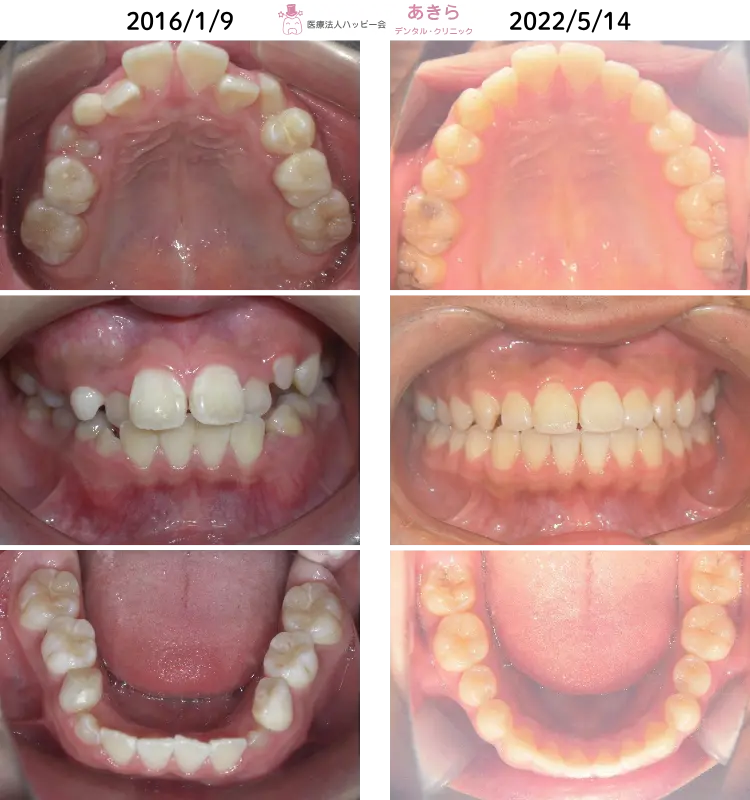

SH療法

SH療法-症例-No.013-右上5番の著しい口蓋側転移位を伴なう症例

山形市の歯医者「あきらデンタル・クリニック」のSH療法の症例をご紹介します。 SH… -